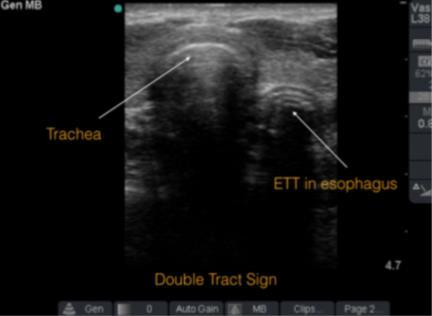

Tips and Tricks:Airway Ultrasound

American College of Emergency Physicians

ACEP Emergency Ultrasound section.

DOI: https://www.acep.org/how-we-serve/sections/emergencyultrasound/news/june-2015/tips-and-tricks-airway-ultrasound/.

Alice Chao, MD, Laleh Gharahbaghian, MD.

Excerpt

In recent years, the use of ultrasound (US) for confirmation of endotracheal tube (ETT) placement has gained increasing popularity. Several techniques already exist to confirm endotracheal tube placement. However, every tool has its limitations, and some are not always available in the emergency department (ED). The likely reason that airway US has gained attention is the ease at which images can be obtained. Airway US for ETT confirmation is best used when the end-tidal CO2 monitor is not accurate, radiology is unavailable, the patient arrives intubated and requires airway confirmation, or the patient does not respond as expected after intubation. There are some tips and tricks that can assist in obtaining the best view.